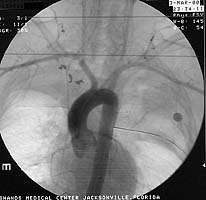

Enclosed are three figures--the CXR of a male with a left to right transmediastinal GSW of upper chest--no hard signs of vascular injury except for about 1000 cc blood out of left chest tube which eventually stopped without surgery. Next is angio #1 showing intimal defect in innominate artery right at the takeoff of the Rt subclavian and carotids. F/U angio one week later--no surgery--documents complete resolution of the intimal injury. There were no symptoms, including the blood from the left chest, attributable to this injury, thus fulfilling the criteria for observation.

Initial Angio